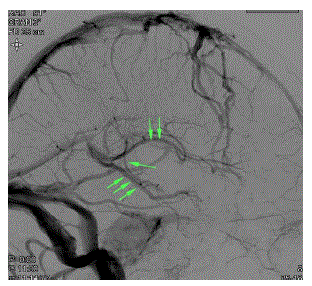

Assinale a alternativa que corresponde à CORRETA topografia do aneurisma cerebral na angiografia abaixo.